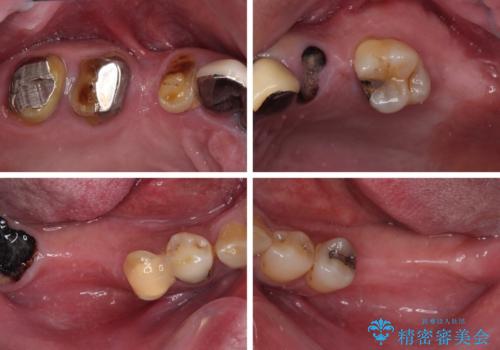

- 奥歯の欠損や、ボロボロになった歯を気にして来院された患者様です。

転勤で東京にいる1年間の間に治療を終えたいとのことで、奥歯のインプラント埋入や前歯部の歯周外科処置など、治癒に時間を要するものから始めていき、治癒期間に根管治療や補綴治療を進めて行くこととしました。

インプラントにより奥歯の咬み合わせが安定し、上顎前歯の歯肉ラインを調整するための骨外科処置により深く咬みこんでいた前歯部も負担のかからない咬み合わせに改善することができました。